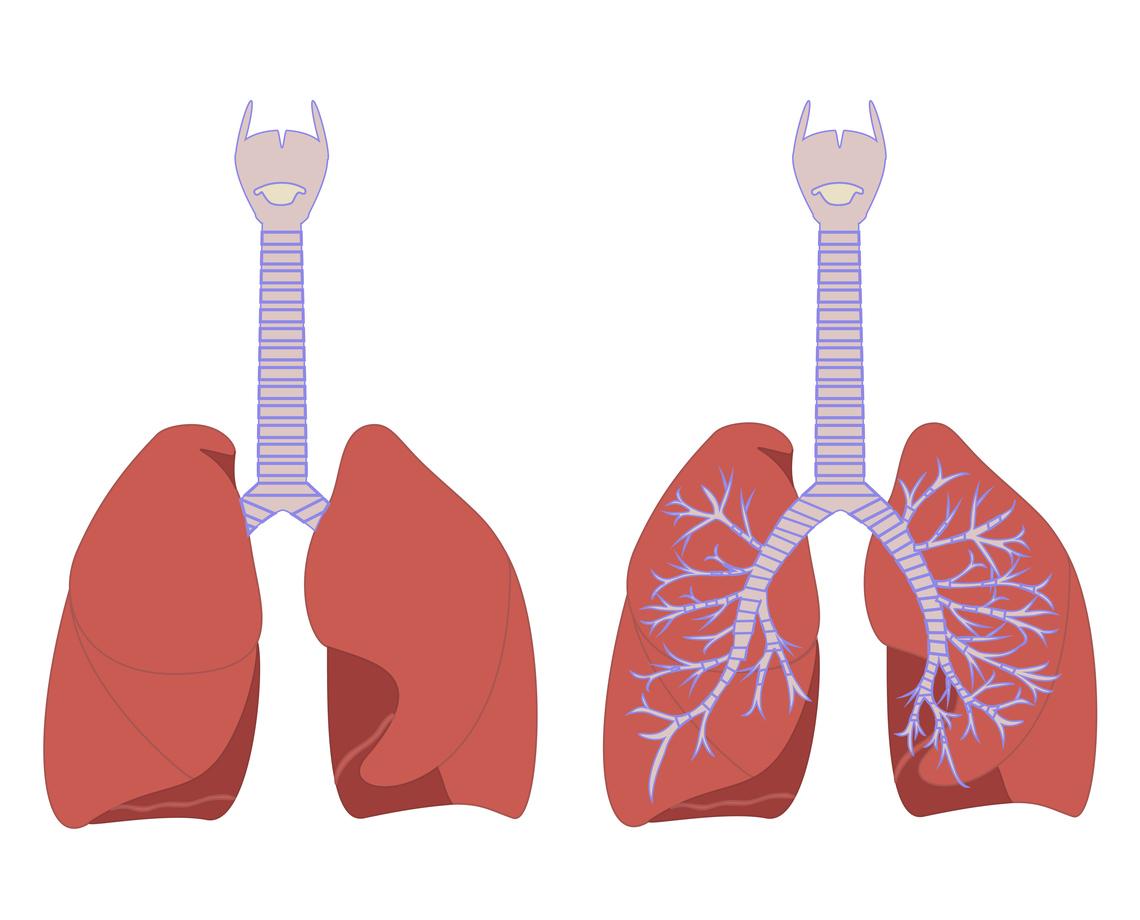

Un organe artificiel proche de l’original

Quelques temps après l’opération, l’organe artificiel implanté est devenu une structure proche de la trachée et des bronches. La membrane interne naturelle, appelée épithélium, s’est reconstituée, aussi de nouveaux cartilages se sont formés, remplaçant ainsi le travail effectué par le stent. D’après les résultats, la mortalité à 90 jours a été de 5%, aucune complication grave n’a été constatée. Au bout de 18,2 mois en moyenne, le stent posé a pu être enlevé chez les patients. Pour une grande majorité, les résultats de la greffe sont positifs. Surtout, certains patients pour qui aucun traitement n’était envisageable, sont aujourd’hui considérés comme guéris par les médecins.